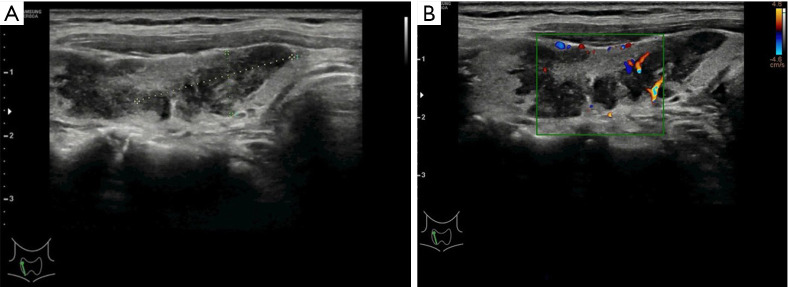

Case description: A 68-year-old woman visited Baoji Central Hospital following ultrasound (US) performed at another hospital indicated a suspicious malignant nodule in her thyroid. Physical examination and thyroid US revealed a hard mass and irregular hypoechoic area in the right lobe, suggesting a possible malignant lesion. Ultrasound-guided FNAC (US-FNAC) was suspicious for PTC. The patient subsequently underwent right thyroid lobectomy and isthmusectomy, and postoperative histopathology revealed an epithelioid granulomatous lesion without tumor tissue. Meanwhile, postoperative serum testing revealed elevated TB-γ interferon concentration, and a specific T lymphocyte testing was positive, indicating a tuberculosis infection. Primary thyroid tuberculosis was ultimately confirmed. Postoperatively, the patient recovered well after surgery and received anti-tuberculosis therapy in a tuberculosis hospital for 1 year.